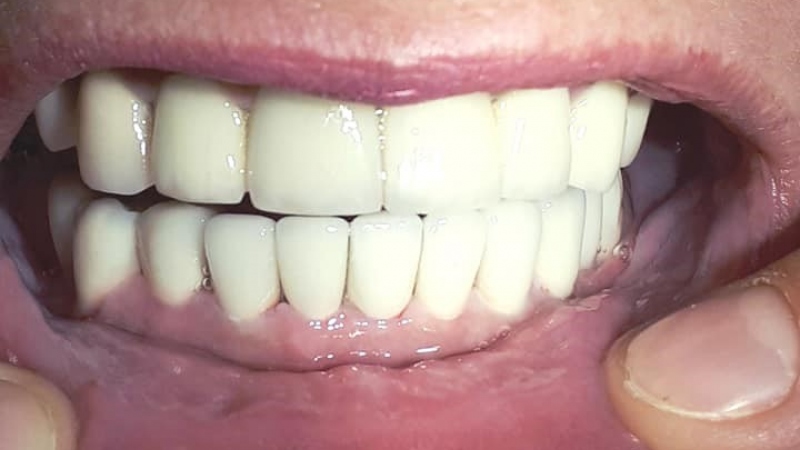

Totálna implantologická náhrada zubov v dolnej čeľusti

Sólo korunky, nahradené implantátmi